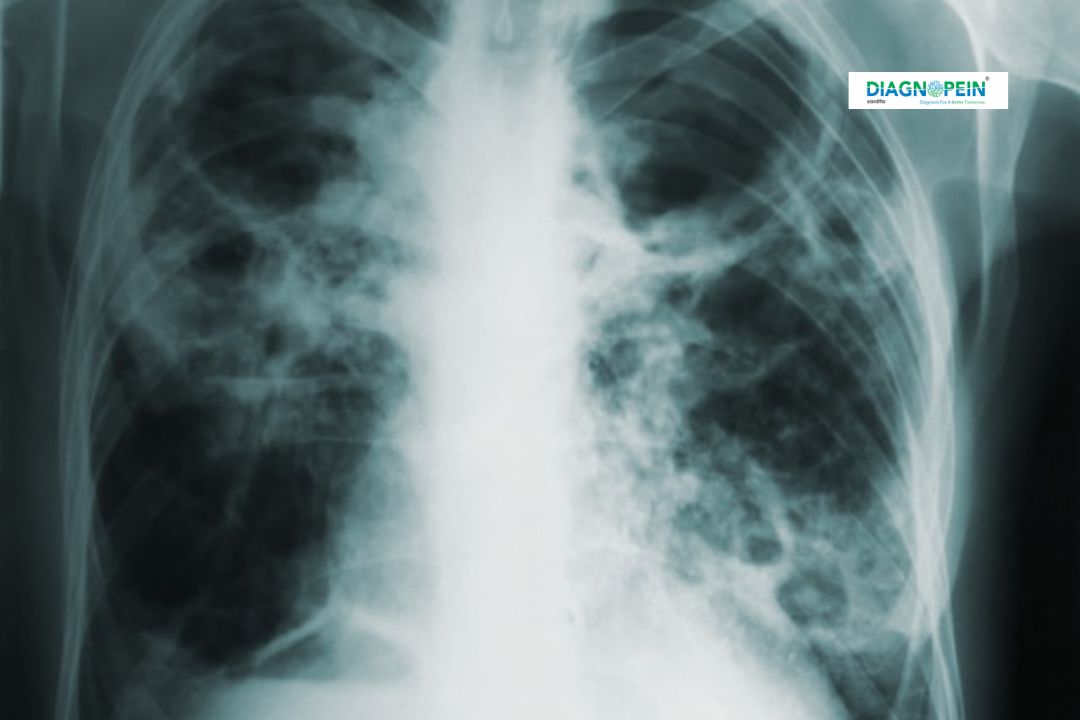

An X-Ray Chest ED (Emergency Department Chest X-Ray) is one of the most rapid, effective, and reliable imaging tests used to evaluate the lungs, heart, chest wall, and nearby structures. At Diagnopein in Karad, our advanced digital X-ray technology ensures clear, high-resolution images for accurate diagnosis. This test is commonly recommended in emergency cases where patients experience sudden chest pain, breathing difficulties, or trauma.

X-Ray Chest ED plays a crucial role in identifying various medical conditions such as pneumonia, lung infections, heart enlargement, tuberculosis, rib fractures, and chest fluid accumulation. Its fast turnaround time and precise imaging make it essential in emergency and regular diagnostic practices.

Doctors rely on X-Ray Chest ED imaging to quickly detect and assess abnormalities in the chest cavity. For patients arriving with acute chest conditions, time is often critical. The test provides instant results that help doctors make accurate clinical decisions without delay.

Common parameters analyzed in an X-Ray Chest ED include:

1. Lung clarity and presence of infection

2. Heart size and contour

3. Position of the diaphragm

4. Presence of pleural effusion

5. Pulmonary vessels visibility

6. Rib alignment and fractures

Each parameter helps in diagnosing respiratory and cardiac conditions efficiently. The precision of imaging at Diagnopein in Karad ensures early detection and better outcomes for every patient.